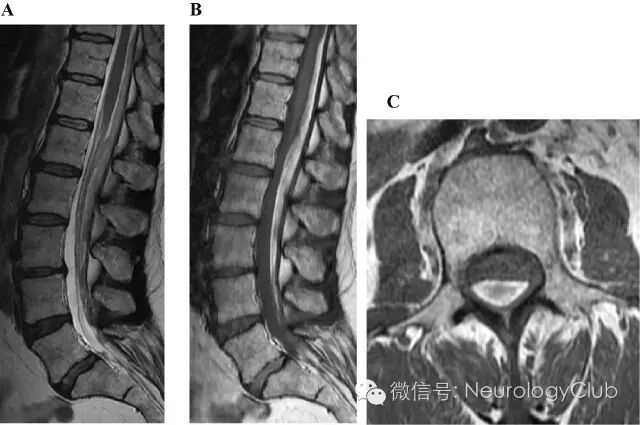

58岁女性,1周前因自发性脑脊液漏(表现为头痛,行头颅MRI提示低颅压)行硬膜外血贴治疗。后续行脊髓MRI检查进一步明确脑脊液漏的情况。患者无明显不适。

(图:A:矢状位T2WI;B:矢状位T1WI;C腰椎横断面T1WI)

硬膜下血肿

现普遍认为硬膜外血贴(EBP)对硬膜穿刺后头痛患者和保守治疗无效的自发性脊髓脑脊液漏患者而言是有效且风险相对低的治疗选择。EBP后的硬膜下血肿(SDH)是罕见的并发症。和Verduzco等报道的类似,本例患者的血肿也长达8个节段。关于EBP后出现SDH,目前主要有3种理论。第一种可能,最初的Tuohy针硬膜穿刺造成了硬膜外和硬膜下腔的交通;第二种可能,EBP时Tuohy针就在硬膜下腔,故而血液注射直接进入硬膜下腔;第三种可能,上述事件同时发生。有报道EBP鞘内注射因操作不当偶会变成硬膜穿刺,MRI可证实存在鞘内血肿。